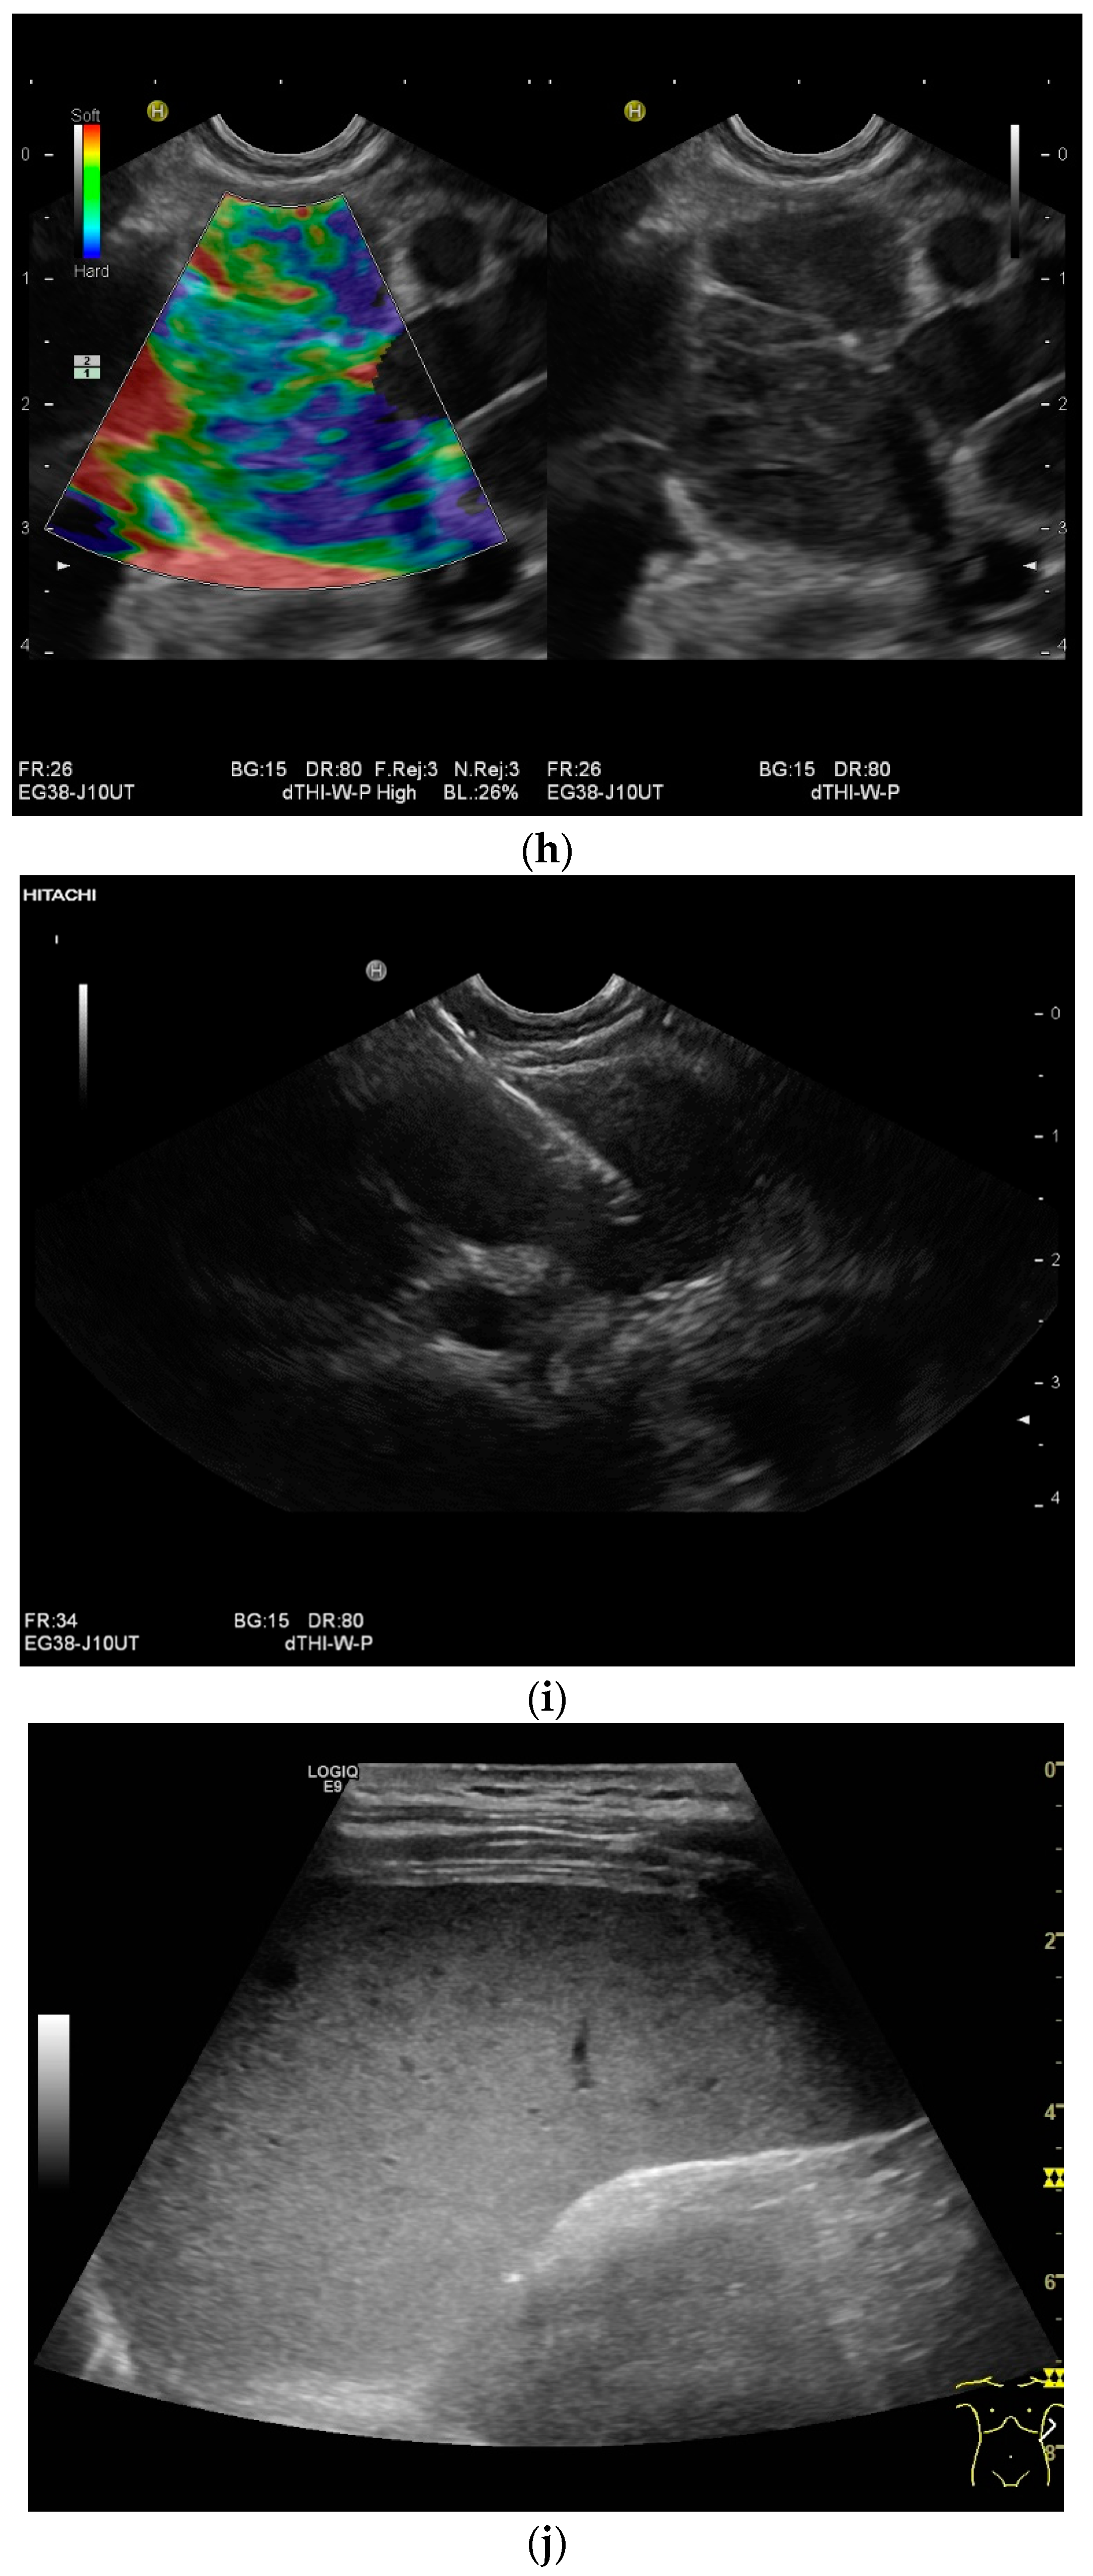

Mediastinal lymph nodes can be biopsied using EUS- or EBUS-guided FNA or FNB. Via paraoesophageal, paragastric, and paraduodenal access, histological specimens can be obtained from further lymph nodes using EUS-guided sampling [41,43,45,46,47,48,49,50] [Figure 2a–m]. The most important differential diagnoses are metastases of malignant tumors, non-Hodgkin’s and Hodgkin’s disease and other infections.

Figure 2.

A case of extrapulmonary tuberculosis: 33 y/o male from a country at high risk of tuberculosis. Thoracic pain and fever led to a suspicion of pericarditis. There was no pericardial effusion. There were no pulmonary infiltrations or pleural effusions in the chest CT, but there were enlarged mediastinal lymph nodes. Ultrasound and CT also showed subdiaphragmal enlarged lymph nodes and small nodular splenic changes. The diagnosis was confirmed using the transgastric EUS-guided biopsy (19 G Olympus) of the lymph nodes in the hepatic hilum. Enlarged lymph nodes in the hepatic hilum (a); adjacent to the pancreatic head (b); transabdominal ultrasound (TUS) using a linear transducer of 9 MHz. The hypoechoic central parts are conspicuous (a,b). Rounded lymph nodes are observed as being peripancreatic (c) and as being in close proximity to the gallbladder wall (d). The lymph nodes are visualized between the markers. In the EUS, paragastric lymph nodes are enlarged, rounded, very hypoechoic, with hypoechoic central parts, and forming conglomerates. A central vascular hilum cannot be delineated in the CDI (e). The hypoechoic central parts are softer during elastography (f). EUS also shows enlarged hypoechoic lymph nodes in the hepatic hilus, with hypoechoic central parts that lack a central vascular hilum (g). Elastographically, the lymph nodes are indifferent (h). The diagnosis is confirmed using EUS-guided biopsy (i) with evidence of granulomatous inflammation, caseous necrosis, detection of acid-fast rods, and Mycobacterium tuberculosis in the PCR. In the spleen, single hypoechoic lesions < 5 mm are visible during transabdominal ultrasound using a linear transducer of 9 MHz. Otherwise, fine-grained hypoechoic lesions can only be guessed at (j). With magnification using a 9 MHz transducer, multiple hypoechoic lesions < 3 mm can be delineated (k). These do not reveal any vessels in the Power Doppler (l). EUS confirms multiple hypoechoic splenic lesions, in line with splenic tuberculosis (m).